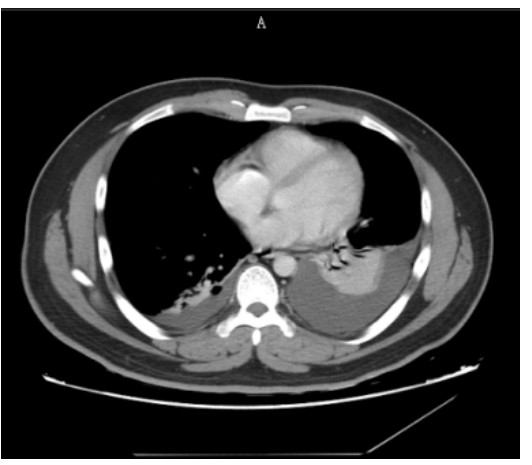

SAP发生呼吸衰竭的原因很复杂,其原因有以下几种。(1)SAP因为炎症反应导致的ARDS(图 1),这是普遍认为的一种原因,但实际上ARDS在SAP患者呼吸衰竭中很多时候是非主要原因。SAP急性期虽然病情进展很快,出现多脏器功能损伤,甚至休克,有类似于脓毒症和感染性休克样的表现,但其炎症反应并不如脓毒症这么强烈,大量的研究可见SAP发生过程其IL-6很少过千,而脓毒症则IL-6动辄大于5 000或10 000,SAP两肺影像学也很少有典型的非心源性肺水肿的双侧阴影,超声下也很少有“B线”表现。但胆道感染引起的脓毒症合并SAP的患者,其ARDS发生率会明显上升。现在随着高脂血症胰腺炎的增加,部分患者到院时同时存在糖代谢障碍,合并有糖尿病酮症,入院前后出现糖尿病酮症昏迷,有些患者会伴有呕吐误吸或者插管时误吸,这类患者在急性期会出现误吸相关的ARDS。(2)SAP是腹腔重症的一种,急性期因为腹膜后急性胰周液体积聚和急性胰周坏死物积聚,导致腹腔压力进行性升高,随之出现横膈抬高,两肺压缩,从而导致“小肺”,这和ARDS的“baby lung(小肺)”不同(图 1: ARDS;图 2、3: 腹内压14 mmHg和23 mmHg的对比,明显看到图 3呈现横膈抬高引起的小肺)。因横膈位置上抬导致小肺是SAP呼吸衰竭的主要原因。(3)两下肺不张(图 4)和胸腔积液(图 5):这两个原因也是导致SAP呼吸衰竭的主要原因,因为膈下刺激,导致两下肺的不张和大量胸腔积液常见于SAP患者,这两种原因导致的呼吸衰竭也和ARDS不同。(4)其他原因:胸腔出血、肺梗死和气胸亦可见于SAP相关呼吸衰竭,但相对少见。

| 图 5 胸腔积液 |

同样特别重要的是监测胸腔积液的变化,SAP患者胸腔积液和肺不张会随着病情进展而进展,床旁超声的动态监测尤为重要,及时的胸腔积液引流,可以有效改善患者氧合。肺不张的原因,一方面与胸腔积液的直接压迫刺激有关,另一方面与横膈抬高及膈下刺激有关,需要适当的正压通气,经鼻高流量吸氧是很好的选择,但其缺点为提供的呼气末正压低,很多时候无法满足肺复张和氧合的需求,这时候就需要及时切换为无创正压通气或者有创通气。有效的镇痛、按病情需要适当的镇静和病情稳定后早期康复的引入,均有利于肺复张。